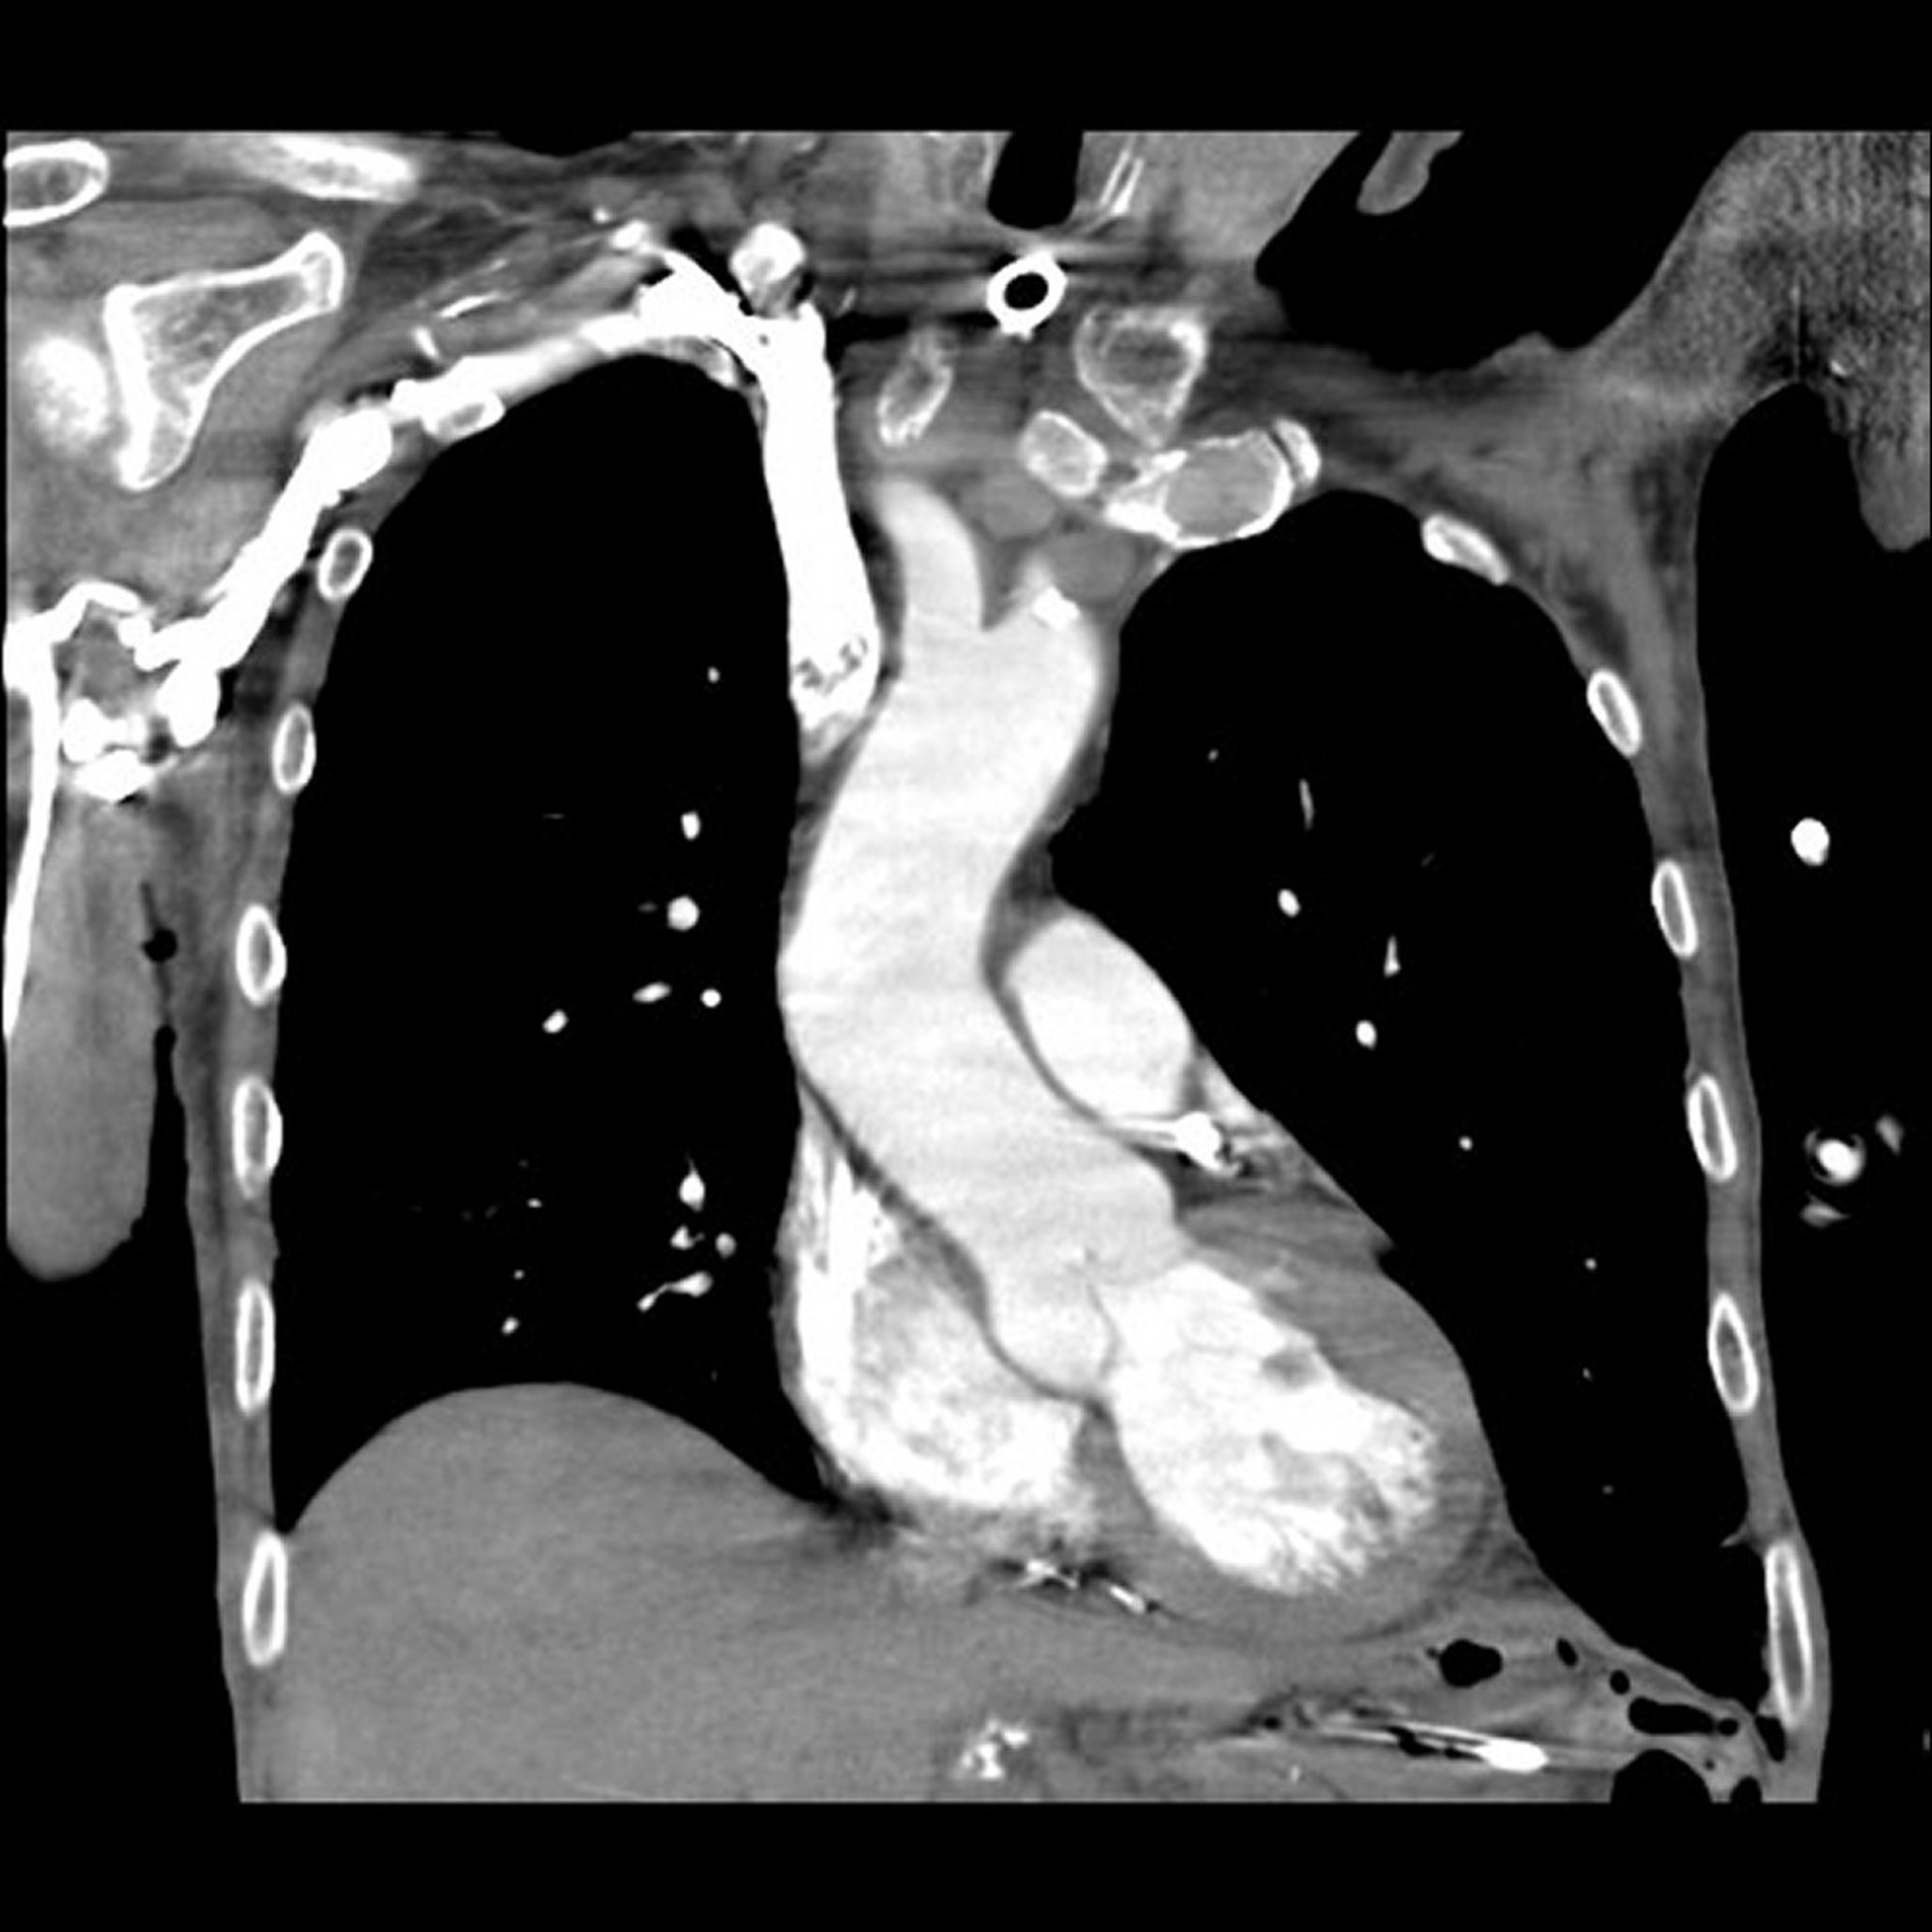

Computed Tomography (CT) Pulmonary Angiography

Image provided by Mehmet Kocak, MD.